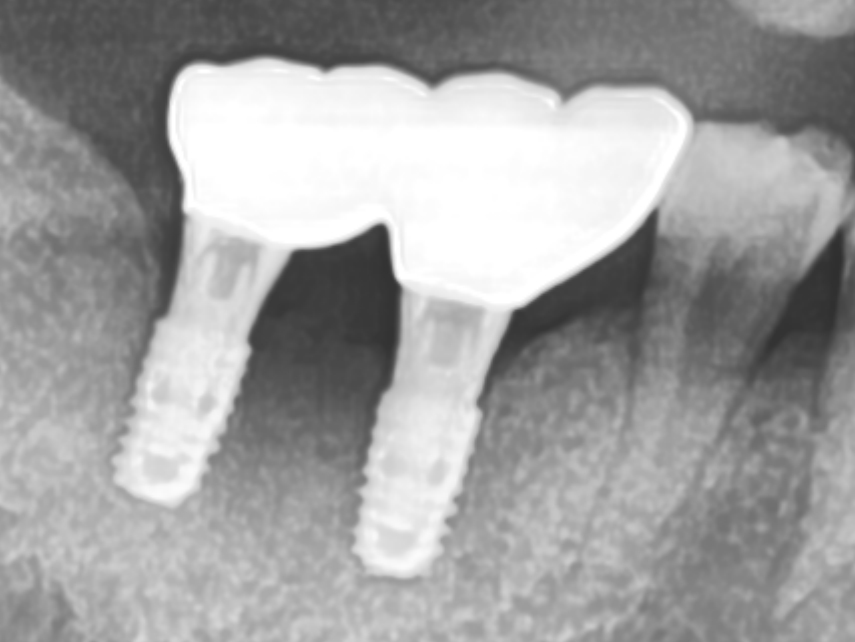

기존 임플란트 염증으로 임플란트제거, 골이식, 새 임플란트식립

치료전 2025.06.09 / 치료후 2025.09.15